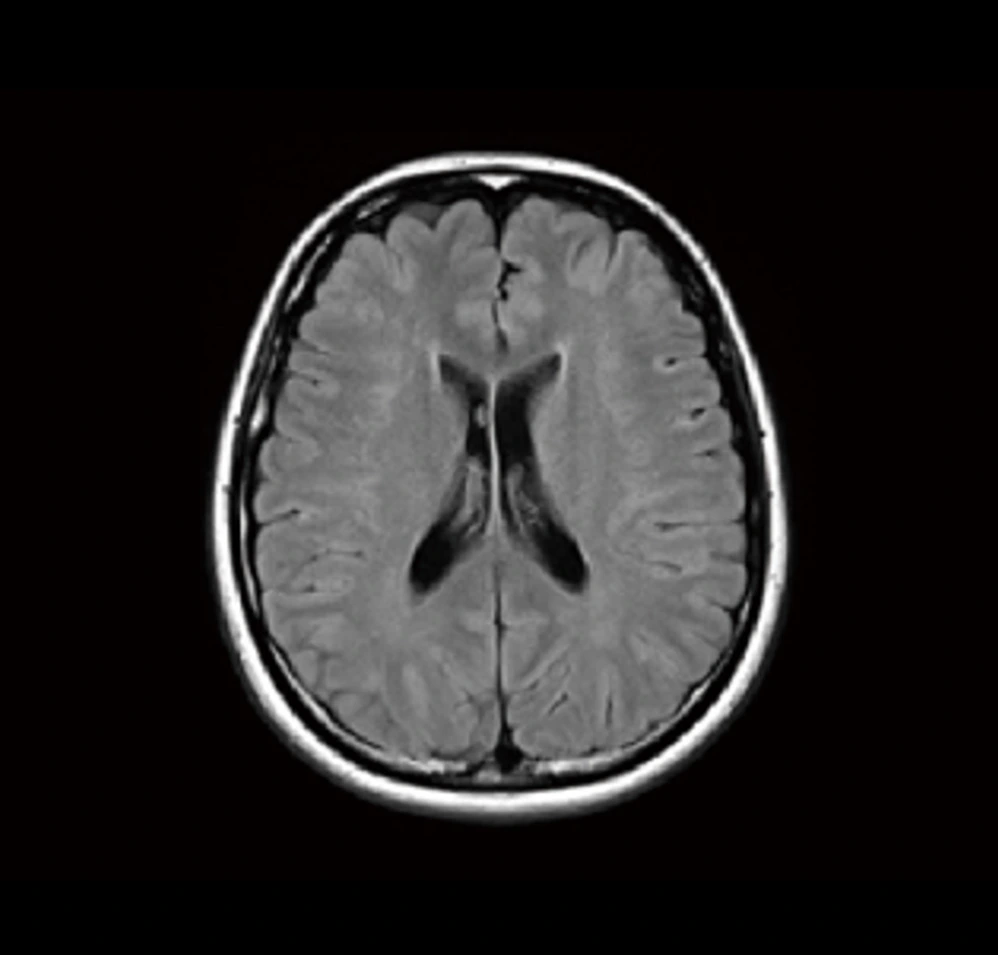

T2強調画像は、水を白く強調するMRIの基本的な撮影方法です。髄液など水成分の多い部位は明るく(白く)映し出されます。

病変部、例えば脳梗塞や脳腫瘍では、組織の障害や浮腫(むくみ)によって水分量が増加するため、その部位が白く描出されます。水や液体成分(髄液、病変部)は白く、脂肪は黒く見えるため、両者を比較することで組織の状態や病変の特徴を総合的に診断できます。解剖学的な構造の評価や病変の検出に広く用いられ、特に脳梗塞では発症時期の推定にも役立ちます。

上の脳画像には白い斑点のようなエリアがあります。

これは白質病変と呼ばれ、脳の血管の健康度の目安になると考えられます。加齢とともに現れる変化ですが、急速な増加は、将来の認知症や脳梗塞のリスク因子と知られています。

| FLAIR | 脳溝や脳室に接する病変の診断に有用 |